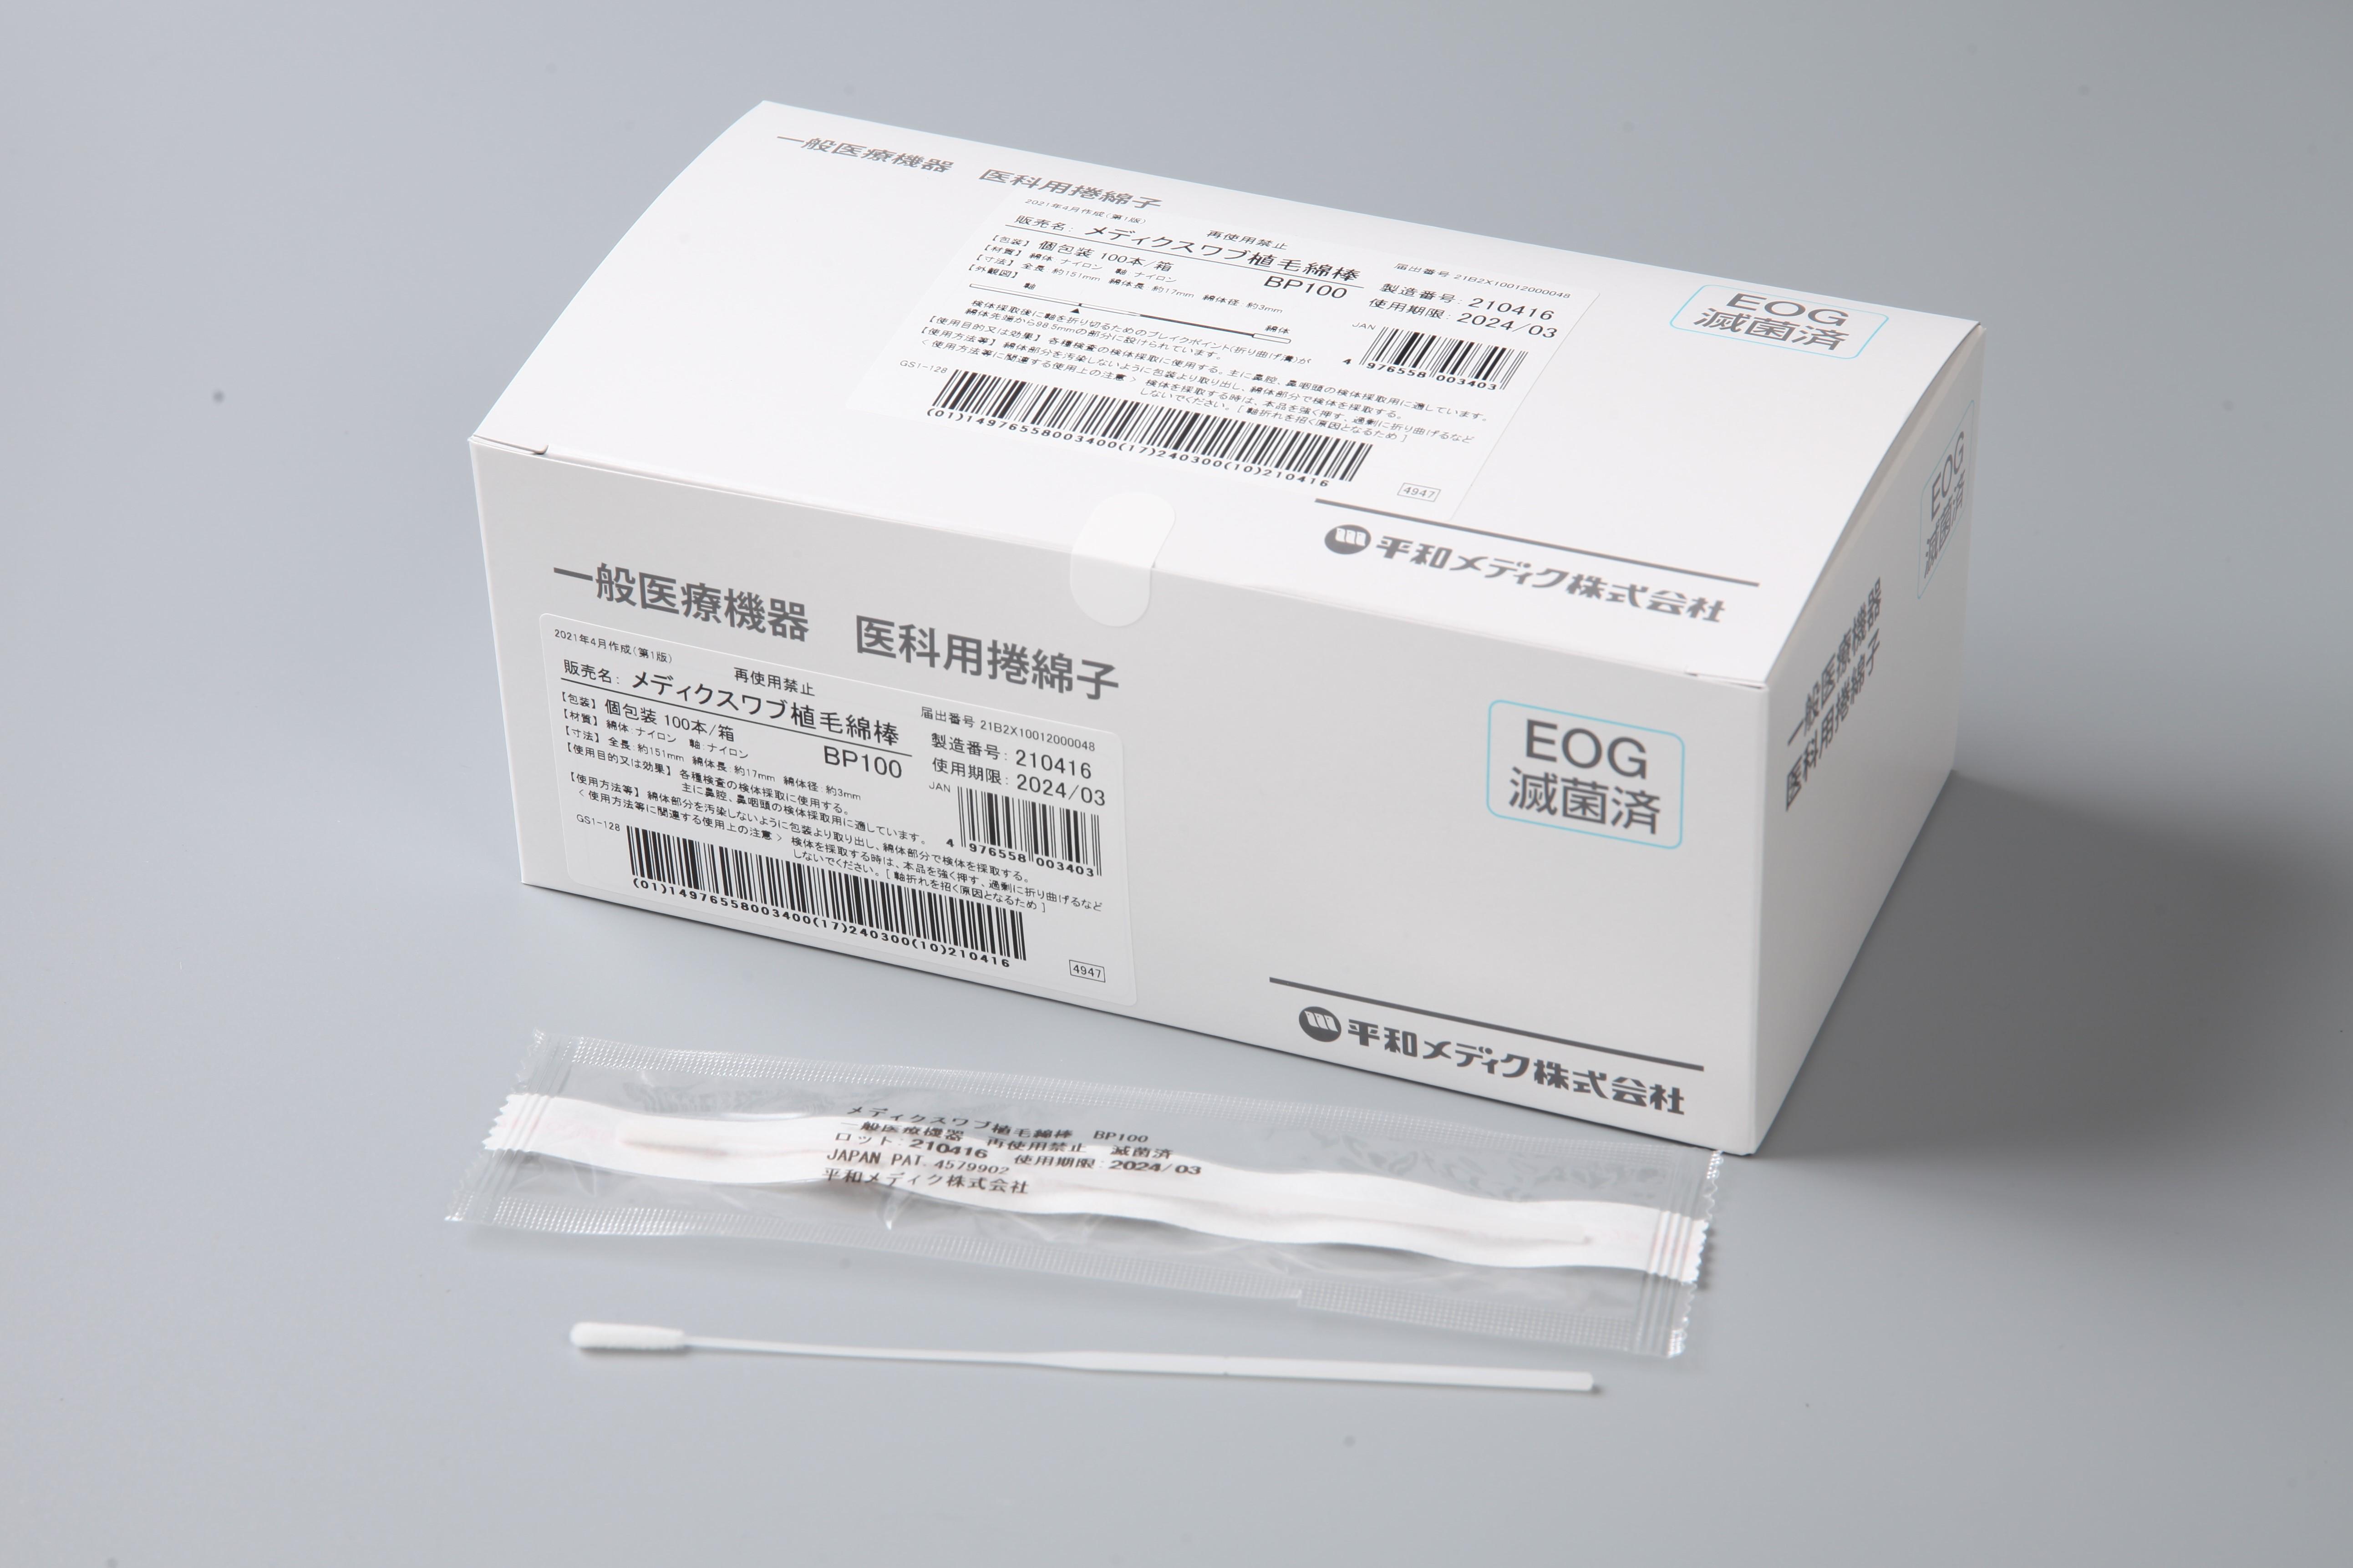

メディクスワブ植毛綿棒NA02 鼻咽頭用 BP100

メディクスワブ植毛綿棒NA02 鼻咽頭用 BP100